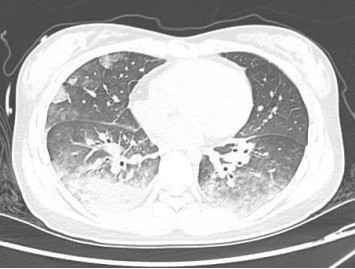

1 资料与方法患者女性,19岁,因“突发胸痛14 h”入院。患者14 h前无明显诱因出现胸骨后疼痛,呈紧缩感,伴有胸闷、呼吸困难,间断咳嗽。近期有听力下降、腹泻病史。8 h前就诊于外院时查体:体温测不出,Bp 53/36 mmHg(1 mmHg=0.133 kPa),呼吸40次/min, 脉搏137次/min,SPO2 93%,神志淡漠,全身皮肤湿冷,黏膜无黄染及出血点,颈静脉无怒张。听诊双肺呼吸音粗,可闻及满肺湿啰音,心音不清,腹部查体无异常,双下肢足背动脉搏动对称。化验结果提示WBC 29.3×109/L,NE 85.4%,TnT 93 ng/L,pro-BNP 2 047 pg/mL,PCT 0.11 ng/mL, 血气分析:pH 7.349,PCO2 31.2mmHg,PO2 67.2 mmHg,HCO3- 17.2 mmol/L,Lac 5.7 mmol/L。心电图提示:窦性心动过速、AVR导联ST段抬高,余导联ST段压低;床旁心脏超声提示EF 52%,二尖瓣中度返流、三尖瓣中重度返流,未见室壁节段性运动性异常。考虑心源性休克,原因尚不明确,给予机械通气、血管活性药物、补液等抗休克治疗,同时联系本院急诊ECMO团队,本院急诊ECMO团队到达现场后,患者突然出现室颤,给予胸外按压及电除颤后逐渐恢复窦律,立即进行V-A ECMO上机指征及预后评分SAVE评分评估,符合V-A ECMO上机适应证,约30 min成功上机运转,流量3.5 L/min,复查外周动脉血气分析: pH 7.305,PCO2 21 mmHg,PO2 73.4 mmHg,HCO3- 10.5 mmol/L,Lac 8.4 mmol/L。后转运至本院急诊病房,转运途中行生命体征、血气分析、ACT等常规监测,至病房后患者ECMO支持下血压仍需大剂量血管活性药物维持且脉压差较小,观察ECMO动静脉管路颜色极为接近,床旁经胸心脏超声提示主动脉瓣重度返流,为明确原因立即行急诊CT检查及床旁经食道超声心动图检查。本院肺CT(图 1)提示肺水肿,床旁经胸心脏超声提示主动脉瓣大量返流但心室收缩可,请超声影像科进一步行床旁经食道超声检查提示无冠窦呈瘤样凸向右房侧,瘤壁上可见宽约0.6 cm破口;主动脉瓣舒张期无冠瓣脱向左室流出道侧(图 2、图 3)。立即请心血管外科会诊,急诊行主动脉瓣机械瓣膜置换术+主动脉窦修补术+房间隔造口术+主动脉球囊反搏置入术+心脏起搏器置入术,术中探查与经食道超声所见相符(图 4、图 5),考虑左心功能差,左心压力较高,行房间隔造口术。术后复查胸片肺水肿基本消失(图 6),继续呼吸机与ECMO支持,因患者肺功能良好,自主呼吸良好,为减少呼吸机相关肺损伤、呼吸机相关肺炎等发生,术后第4天神志清醒后拔除气管插管,机械通气减轻左心前后负荷的作用去除后,继续ECMO与IABP支持,ECMO增加左心后负荷时IABP可降低左室后负荷,达到左心减压的目的,术后第10天心功能恢复,下调ECMO流量后循环可维持,予以撤离ECMO,术后第12天撤离IABP,后停用肝素持续泵入抗凝,达肝素皮下注射联用华法林口服抗凝3 d后,单用华法林口服抗凝,维持INR达标,在康复期间患者活动时左下肢疼痛,左侧足背动脉搏动减弱,下肢动静脉超声提示左侧股浅动脉血栓形成,期间增加华法林剂量后血栓未见明显变化,后行下肢股浅动脉切开取栓术,术后33 d患者完全康复顺利出院。

| 图 1 术前肺CT |

主动脉窦瘤较小或未破裂时患者可能完全没有症状,破裂后根据破口大小、破入部位的不同会产生不同的血流动力学变化,产生相应的临床表现也会不同。当破入右心时,主动脉与右心之间的压力差增大,引起右心容量负荷增加,严重者可出现肺动脉高压;与此同时,因大量左向右分流导致体循环血流量明显减少,易进展为急性心源性休克[6-8]。本案例患者术中探查考虑为先天性无冠窦瘤,既往窦瘤未破裂时无明显症状,破裂后患者突发胸痛、胸闷、呼吸困难,很快出现心源性休克,且V-A ECMO支持下患者血压仍需大剂量血管活性药物维持且脉压差较小,与窦瘤破入右房后体循环血流量明显减少出现的血流动力学改变相符,右心容量负荷增加导致的肺水肿与肺CT表现一致。